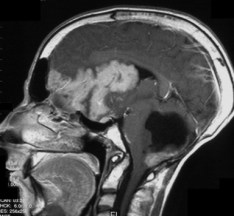

l’imagerie

elle peut être très évocatrice, montrant une tumeur spontanément hyperdense en scanner, avec une prise de contraste hétérogène et une hypercellularité bien montrée par la séquence en diffusion.

l’aspect radiologique peut cependant être trompeur.

on recherche systématiquement des métastase par l‘IRM cranio-spinale.